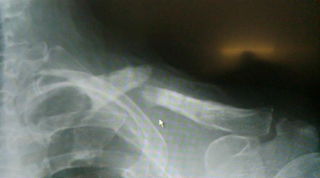

某病院で手術後半年でプレート除去。その後すぐに再骨折してしまい、再手術しにくいとでライダーが紹介されて来院しました。当院オリジナル超音波骨治療器と理学療法、物理療法で再手術せずに完全に骨癒合してました。

上の写真が某病院から送られてきた時の写真で下の写真が当院治療にて骨癒合した写真です。

このプロライダーは今回の骨折でかなり苦しんだみたいですが、来シーズンから復帰は十分可能です。